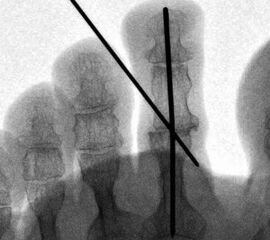

Die vorbereitenden Operationsschritte werden im Abschnitt „PIP-Arthrodese mit K-Draht-Fixierung“ in den Abbildungen 1.1 bis 1.7 beschrieben.

• Eine Röntgenkontrolle wird 6 Wochen postoperativ durchgeführt (Fuß belastet in zwei Ebenen). Besonders geachtet wird auf eine knöcherne Konsolidierung der Arthrodese und auf die Lage eines gegebenenfalls verwendeten intramedullären Implantats.

• Unzureichende Knochenresektion und die persistierende Spannung um Bereich des PIP-Gelenkes kann zu einem Rezidiv der Deformität führen. In diesem Fall ist eine weitere Knochenresektion erforderlich. Zur besseren Stabilisierung können zwei K-Drähte für die Dauer von 4-5 Wochen verwendet werden.